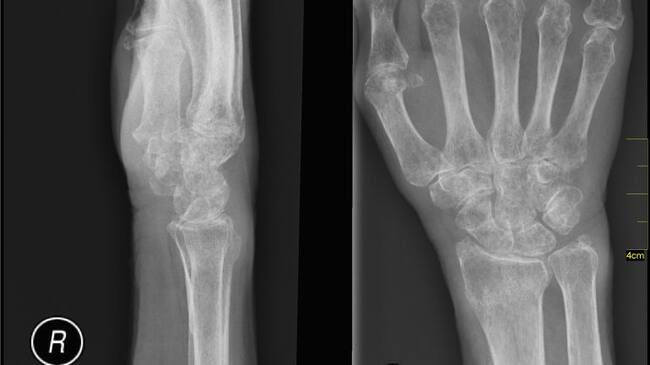

Una radiografía de la columna vertebral o de la cadera puede mostrar fractura o aplastamiento vertebral. Sin embargo, las radiografías simples de otros huesos no son muy precisas para predecir si usted es propenso o no a tener osteoporosis. Es posible que necesite otros exámenes de sangre y orina si se cree que su osteoporosis se debe a una afección más que a la simple pérdida ósea normal que se observa al envejecer.